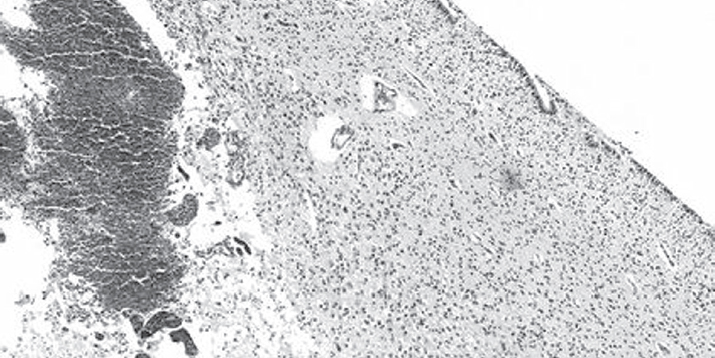

This article focuses on the problem of intraventricular hemorrhage in preterm infants with low and extremely low body weight. Premature newborns are most susceptible to this pathology due to the morpho-functional immaturity of brain tissues and blood vessels. Pathological factors lead to lesion of the vessel wall and a massive hemorrhage in the cavity of the ventricles, sometimes with a breakthrough into the white matter. The morphological findings of hemorrhage in the lateral ventricles of the brain in a child born with extremely low body weight are presented on an example of a clinical case. The article presents a description of the morphology of damage to the germinal matrix and choroid plexus as one of the most common sources of hemorrhage. The main attention is paid to the state of the blood vessels: arterioles, venules, capillaries. Possible causes and consequences of vascular injury in the periventricular region are indicated here. According to the recent studies, intraventricular hemorrhage appears more often due to damage to the choroid plexus in children born at 37 weeks of gestation and later. In this report we consider the problem of hemorrhage from the reducing germinal matrix’s vessels into the subependymal region with spreading into the white matter and lateral ventricles.